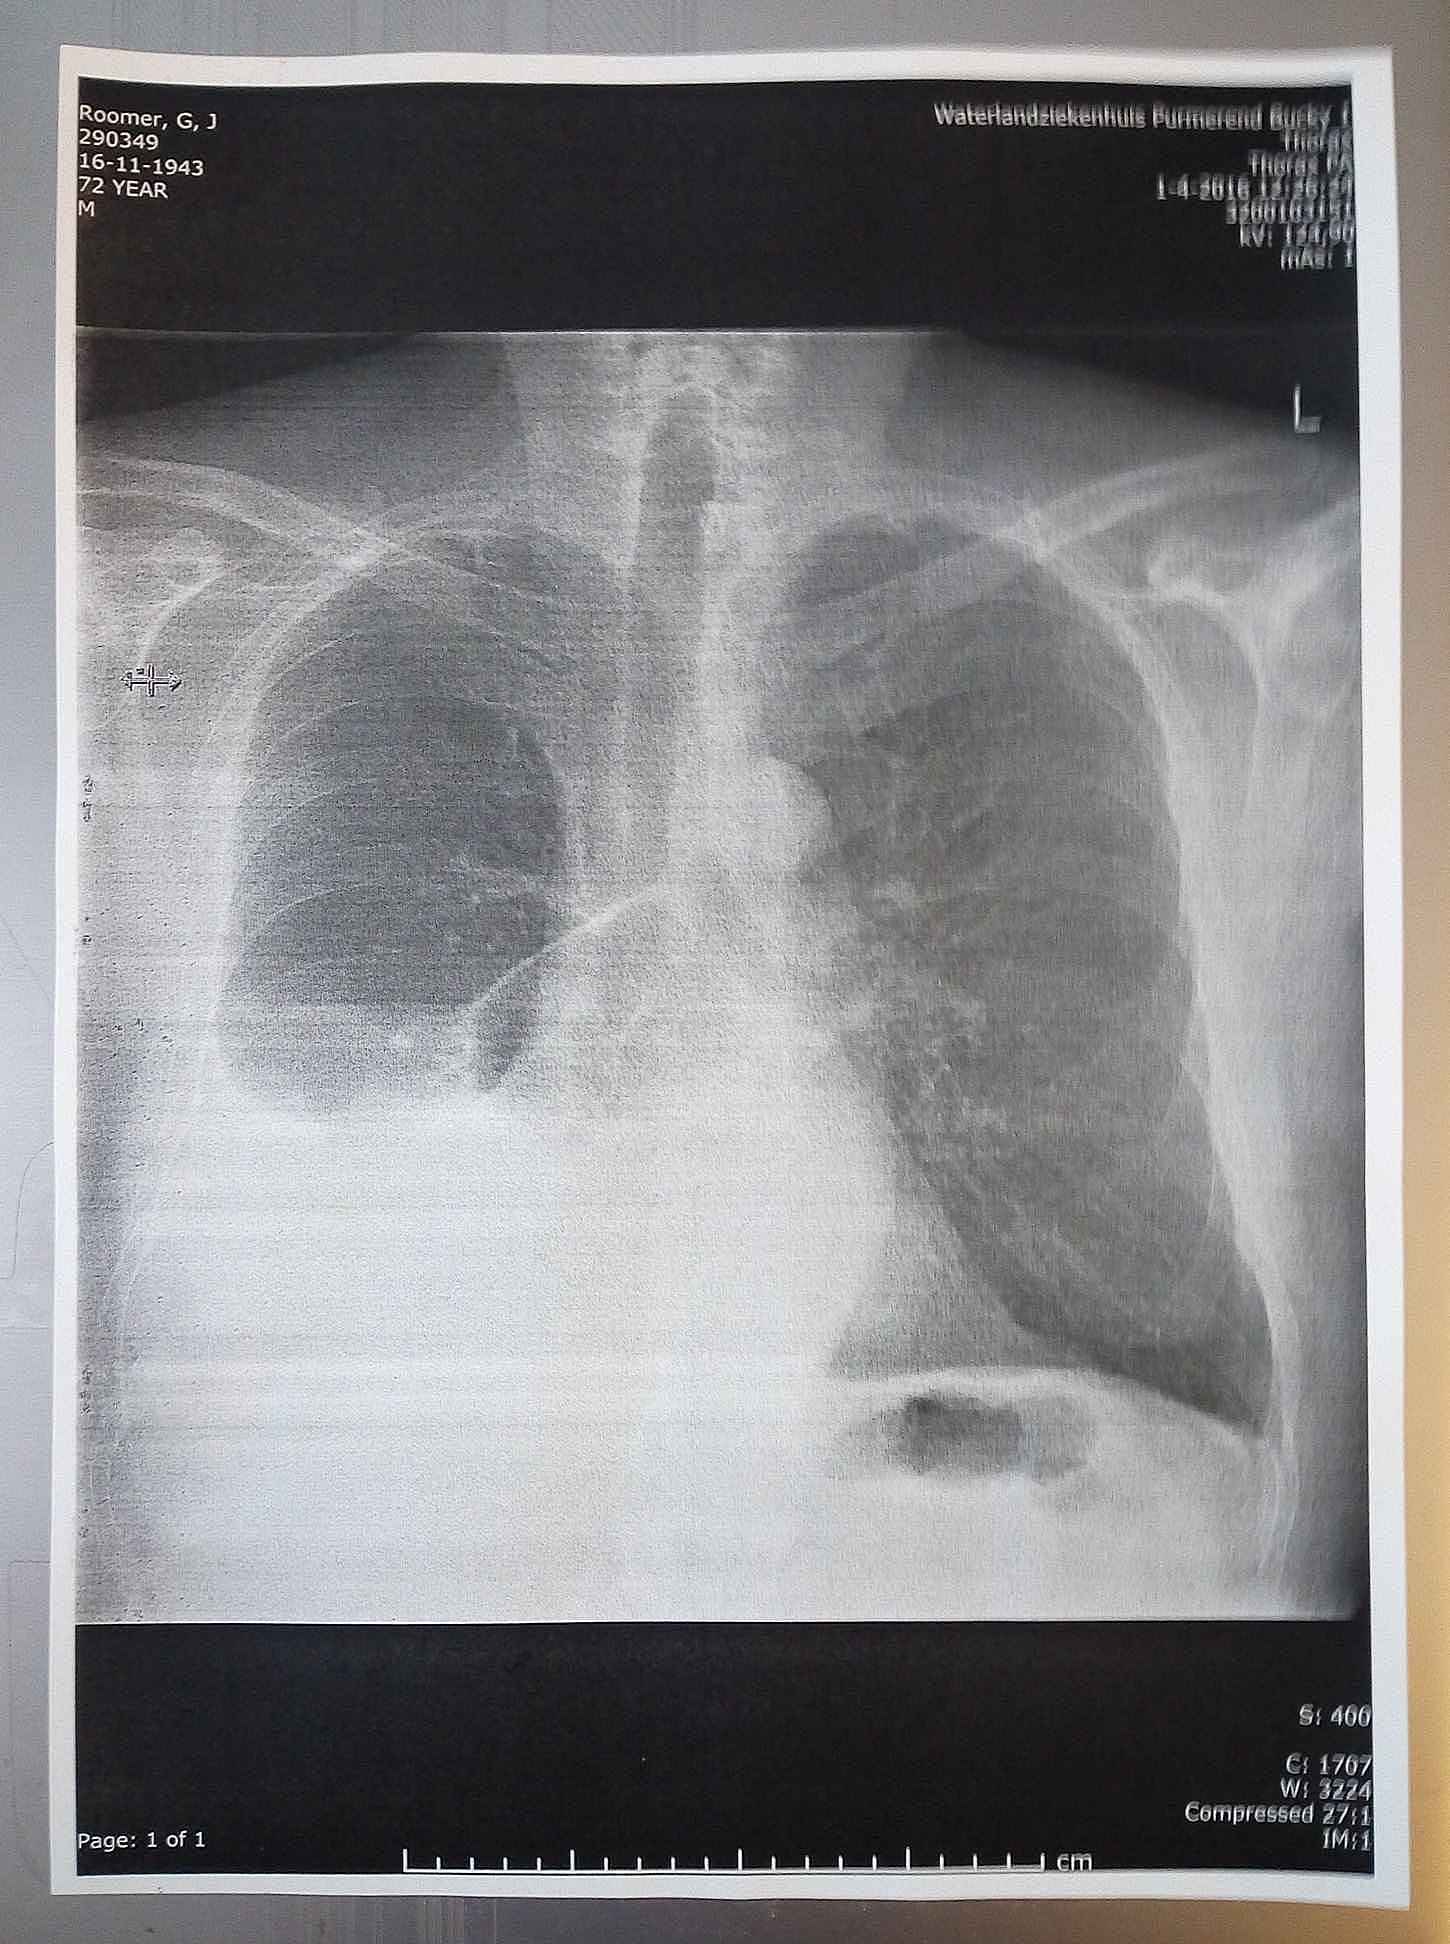

Half maart 2016